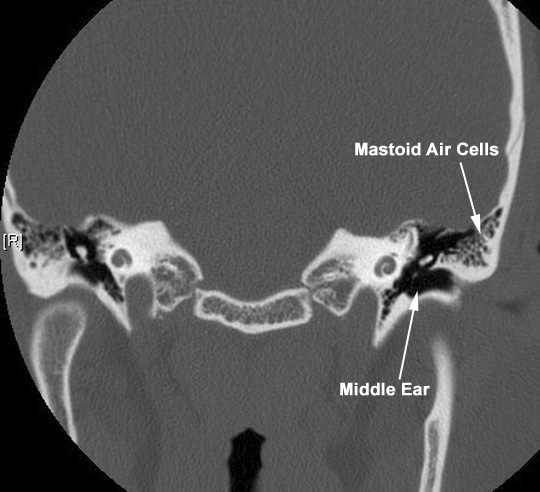

Appreciate the relationship of the middle ear to mastoid air cells. Click the image for labeling.